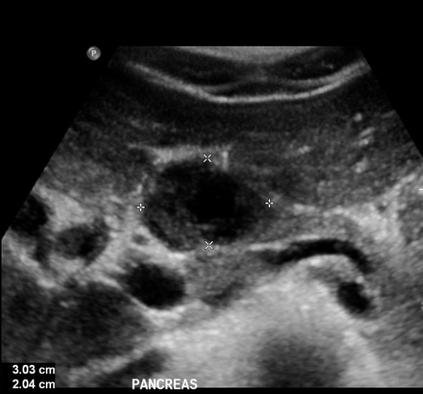

In this study, we aim to initiate the development of Radiology Foundation Model, termed as RadFM.We consider the construction of foundational models from the perspectives of data, model design, and evaluation thoroughly. Our contribution can be concluded as follows: (i), we construct a large-scale Medical Multi-modal Dataset, MedMD, consisting of 16M 2D and 3D medical scans. To the best of our knowledge, this is the first multi-modal dataset containing 3D medical scans. (ii), We propose an architecture that enables visually conditioned generative pre-training, allowing for the integration of text input interleaved with 2D or 3D medical scans to generate response for diverse radiologic tasks. The model was initially pre-trained on MedMD and subsequently domain-specific fine-tuned on RadMD, a radiologic cleaned version of MedMD, containing 3M radiologic visual-language pairs. (iii), we propose a new evaluation benchmark that comprises five tasks, aiming to comprehensively assess the capability of foundation models in handling practical clinical problems. Our experimental results confirm that RadFM significantly outperforms existing multi-modal foundation models. The codes, data, and model checkpoint will all be made publicly available to promote further research and development in the field.